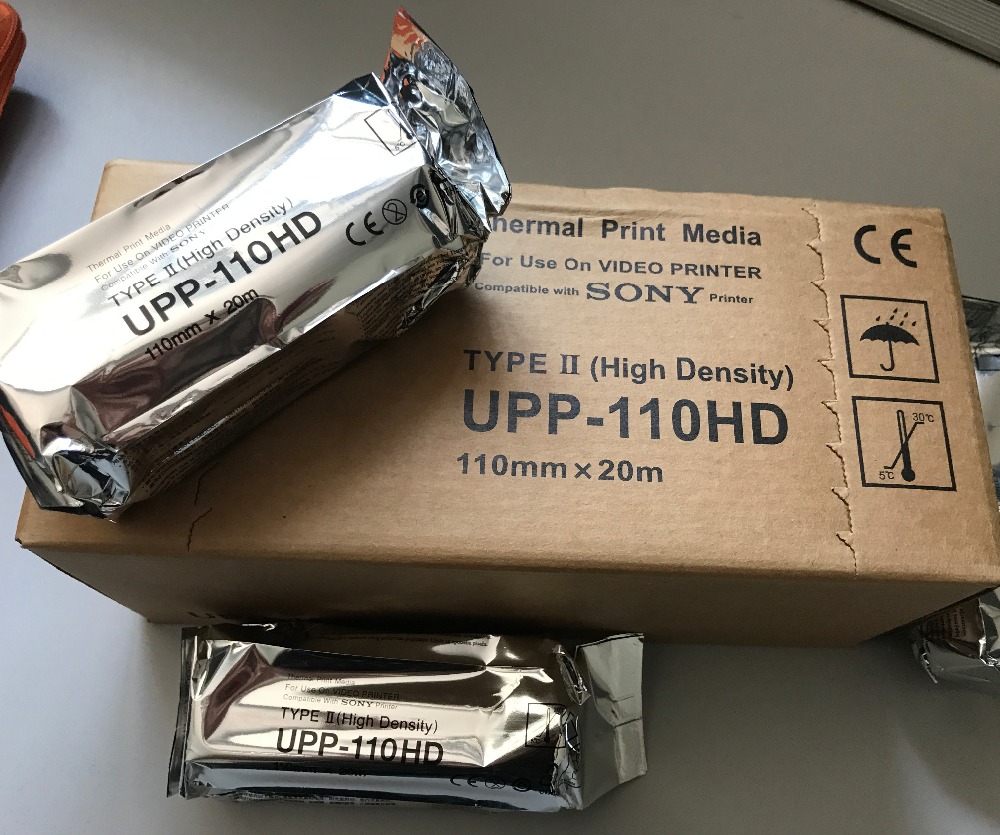

Ultrasound Paper Rolls UPP-110HD_Type II

PRODUCT INTRODUCTION

Thermal Video Printer Paper

1.Glossy Type Paper(Type V).

2.Each roll is packed in individual pack

3.High resolution and preservation of printed video image

4.110S,110HG,110HD

5.Package: 10 rolls/box, 10boxs/cartons

ultrasound paper 110s

|

110mmx20m

|

100rolls/carton

ultrasound paper high glossy

|

110mmx18m

|

100rolls/carton

ultrasound paper high density

|

110mmx20m

|

100rolls/carton